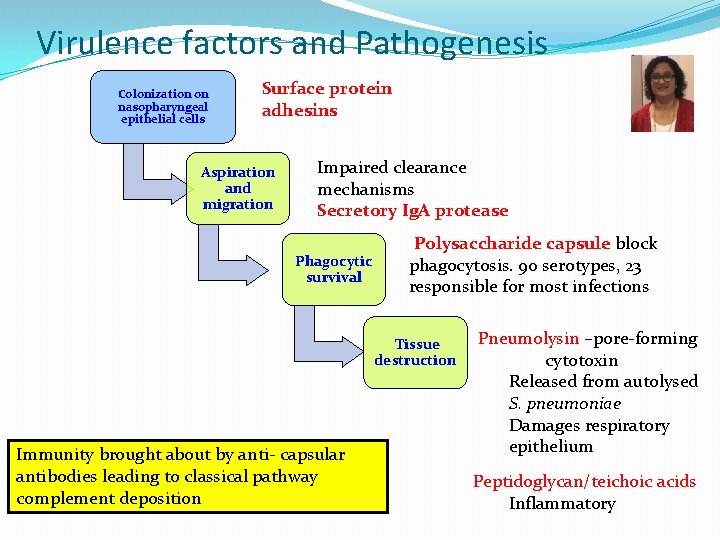

Virulence factors and Pathogenesis Colonization on nasopharyngeal epithelial cells Surface protein adhesins Aspiration and migration Impaired clearance mechanisms Secretory Ig. A protease Phagocytic survival Polysaccharide capsule block phagocytosis. 90 serotypes, 23 responsible for most infections Tissue destruction Immunity brought about by anti- capsular antibodies leading to classical pathway complement deposition Pneumolysin –pore-forming cytotoxin Released from autolysed S. pneumoniae Damages respiratory epithelium Peptidoglycan/teichoic acids Inflammatory

Streptococcus pneumoniae Virulence Factors � Polysaccharide capsule – essential for virulence � Antiphagocytic � 90 serotypes, 23 responsible for most infections � Ig. A protease � Colonization � Autolysin � Release of intracellular virulence factors and cell wall fragments � Pneumolysin –pore-forming toxin � Released from autolysed S. pneumoniae � Damages respiratory epithelium � Peptidoglycan/teichoic acids � Inflammatory Damage of epithelium stimulates outpouring of fluid, red blood cells, and leukocytes from alveoli productive cough with blood 19